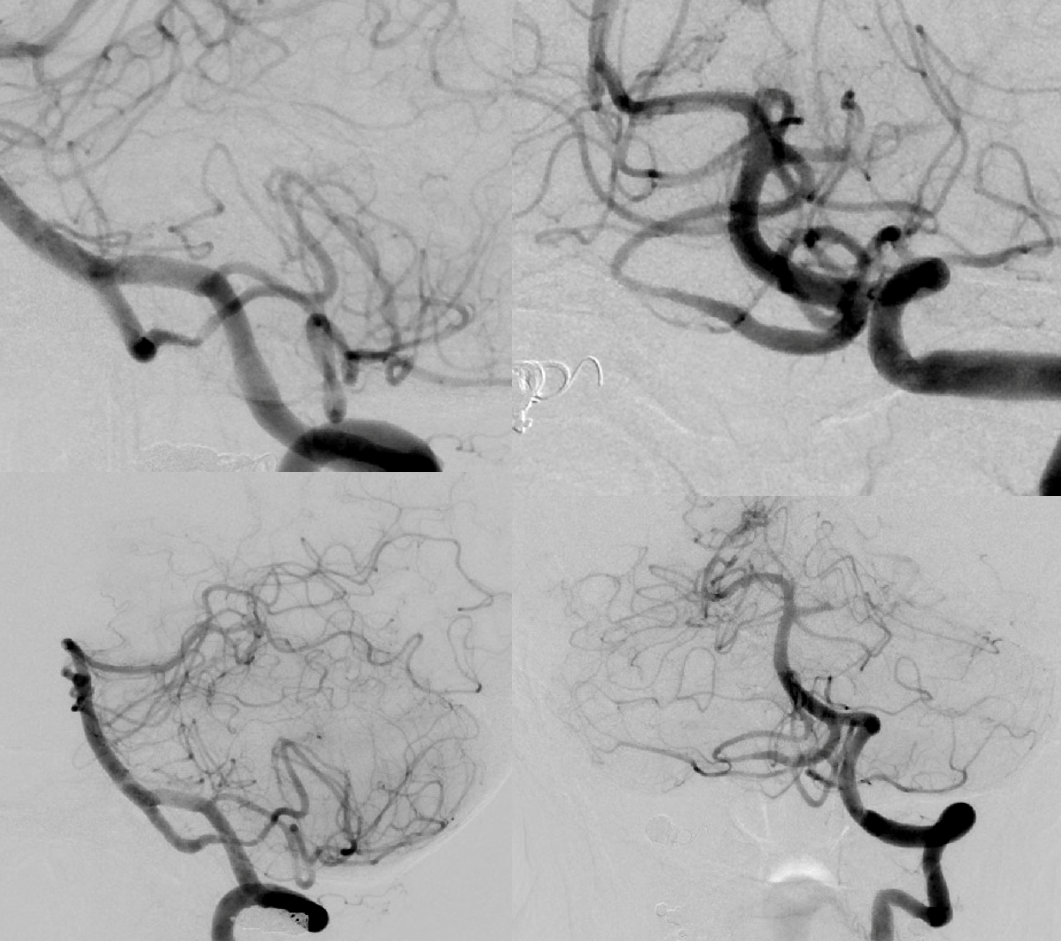

PLan to sacrifice right vert and Pipe across VB junction into PICA.

Could one argue that pipe is not necessary. Possibly. The main point is that this needs aggressive solutions before its too late. Flow reversal is key. What if sac is not enough and mass effect worsens? Take that chance or maximize odds of success with a Pipe? We did what we did

Angio